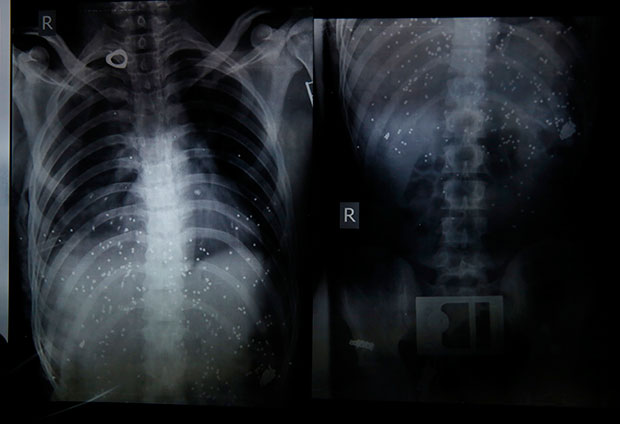

Sta Korona Cini Plucima Objavljeni Rendgenski Snimci Preminulih Ljudi

Sta Korona Cini Plucima Objavljeni Rendgenski Snimci Preminulih Ljudi Na Kojima Se Vide Koje Su Posledice Virusa Foto

Sokantne Fotografije Pokazuju Koliko Je Korona Virus Unistio Pluca Prvim Zrtvama Bolesti U Italiji Najnovije Vesti Srbija Danas

Sokantne Snimke Pluca Dvoje Kineza Prvih Europskih Zrtava 24sata